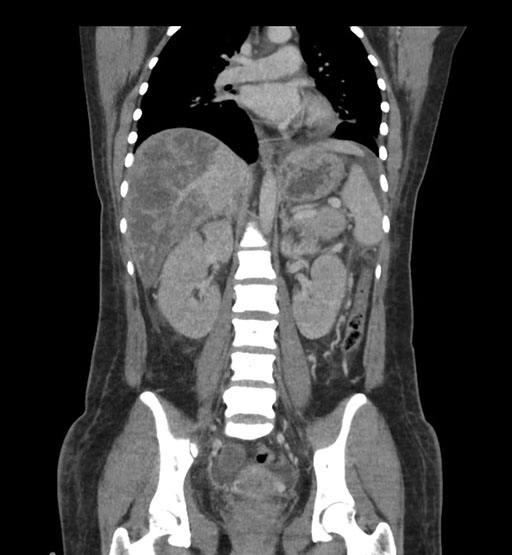

Imaging Analysis

Look through the patient's CT scan to identify any areas of concern for the necessary procedure.

Coronal Arterial

Coronal Venous

Based on initial findings, which issue(s) would you be most concerned about?